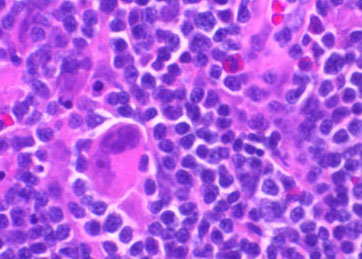

Micro: LN c diffuse nodal involvement showing pseudofollicular architecture (no true mantle zone) c large pale prolif centers c prolymphocytes (>11%; sm to med size cells c clumped chromatin and small nucleoli), paraimmunoblasts (larger, c round to oval nuclei, central red nucleoli)

CLL pseudofollicle (proliferation center). Little lymphocytes with small cytoplasm on the left. On the right, paraimmunoblasts are larger, with a little more cytoplasm, with prolymphocytes (black arrow)showing dispersed chromatin, and the red arrow to paraimmunoblasts with prominent central nucleolus (called "paraimmunoblasts" because typically smaller than B-type immunoblasts).